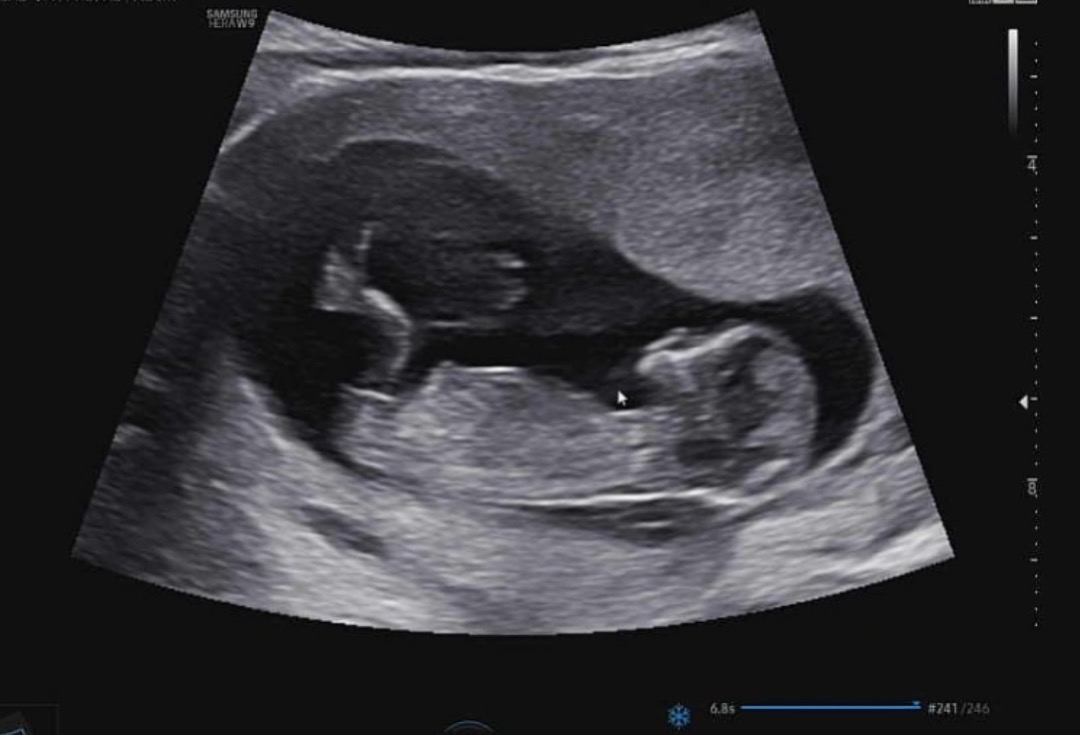

11주 4일 각도법 궁금해요 !!

각도법 마구 참견 부탁드려요! 다른분들은 어떻게 보일지 넘 궁금해요 !! 🥹